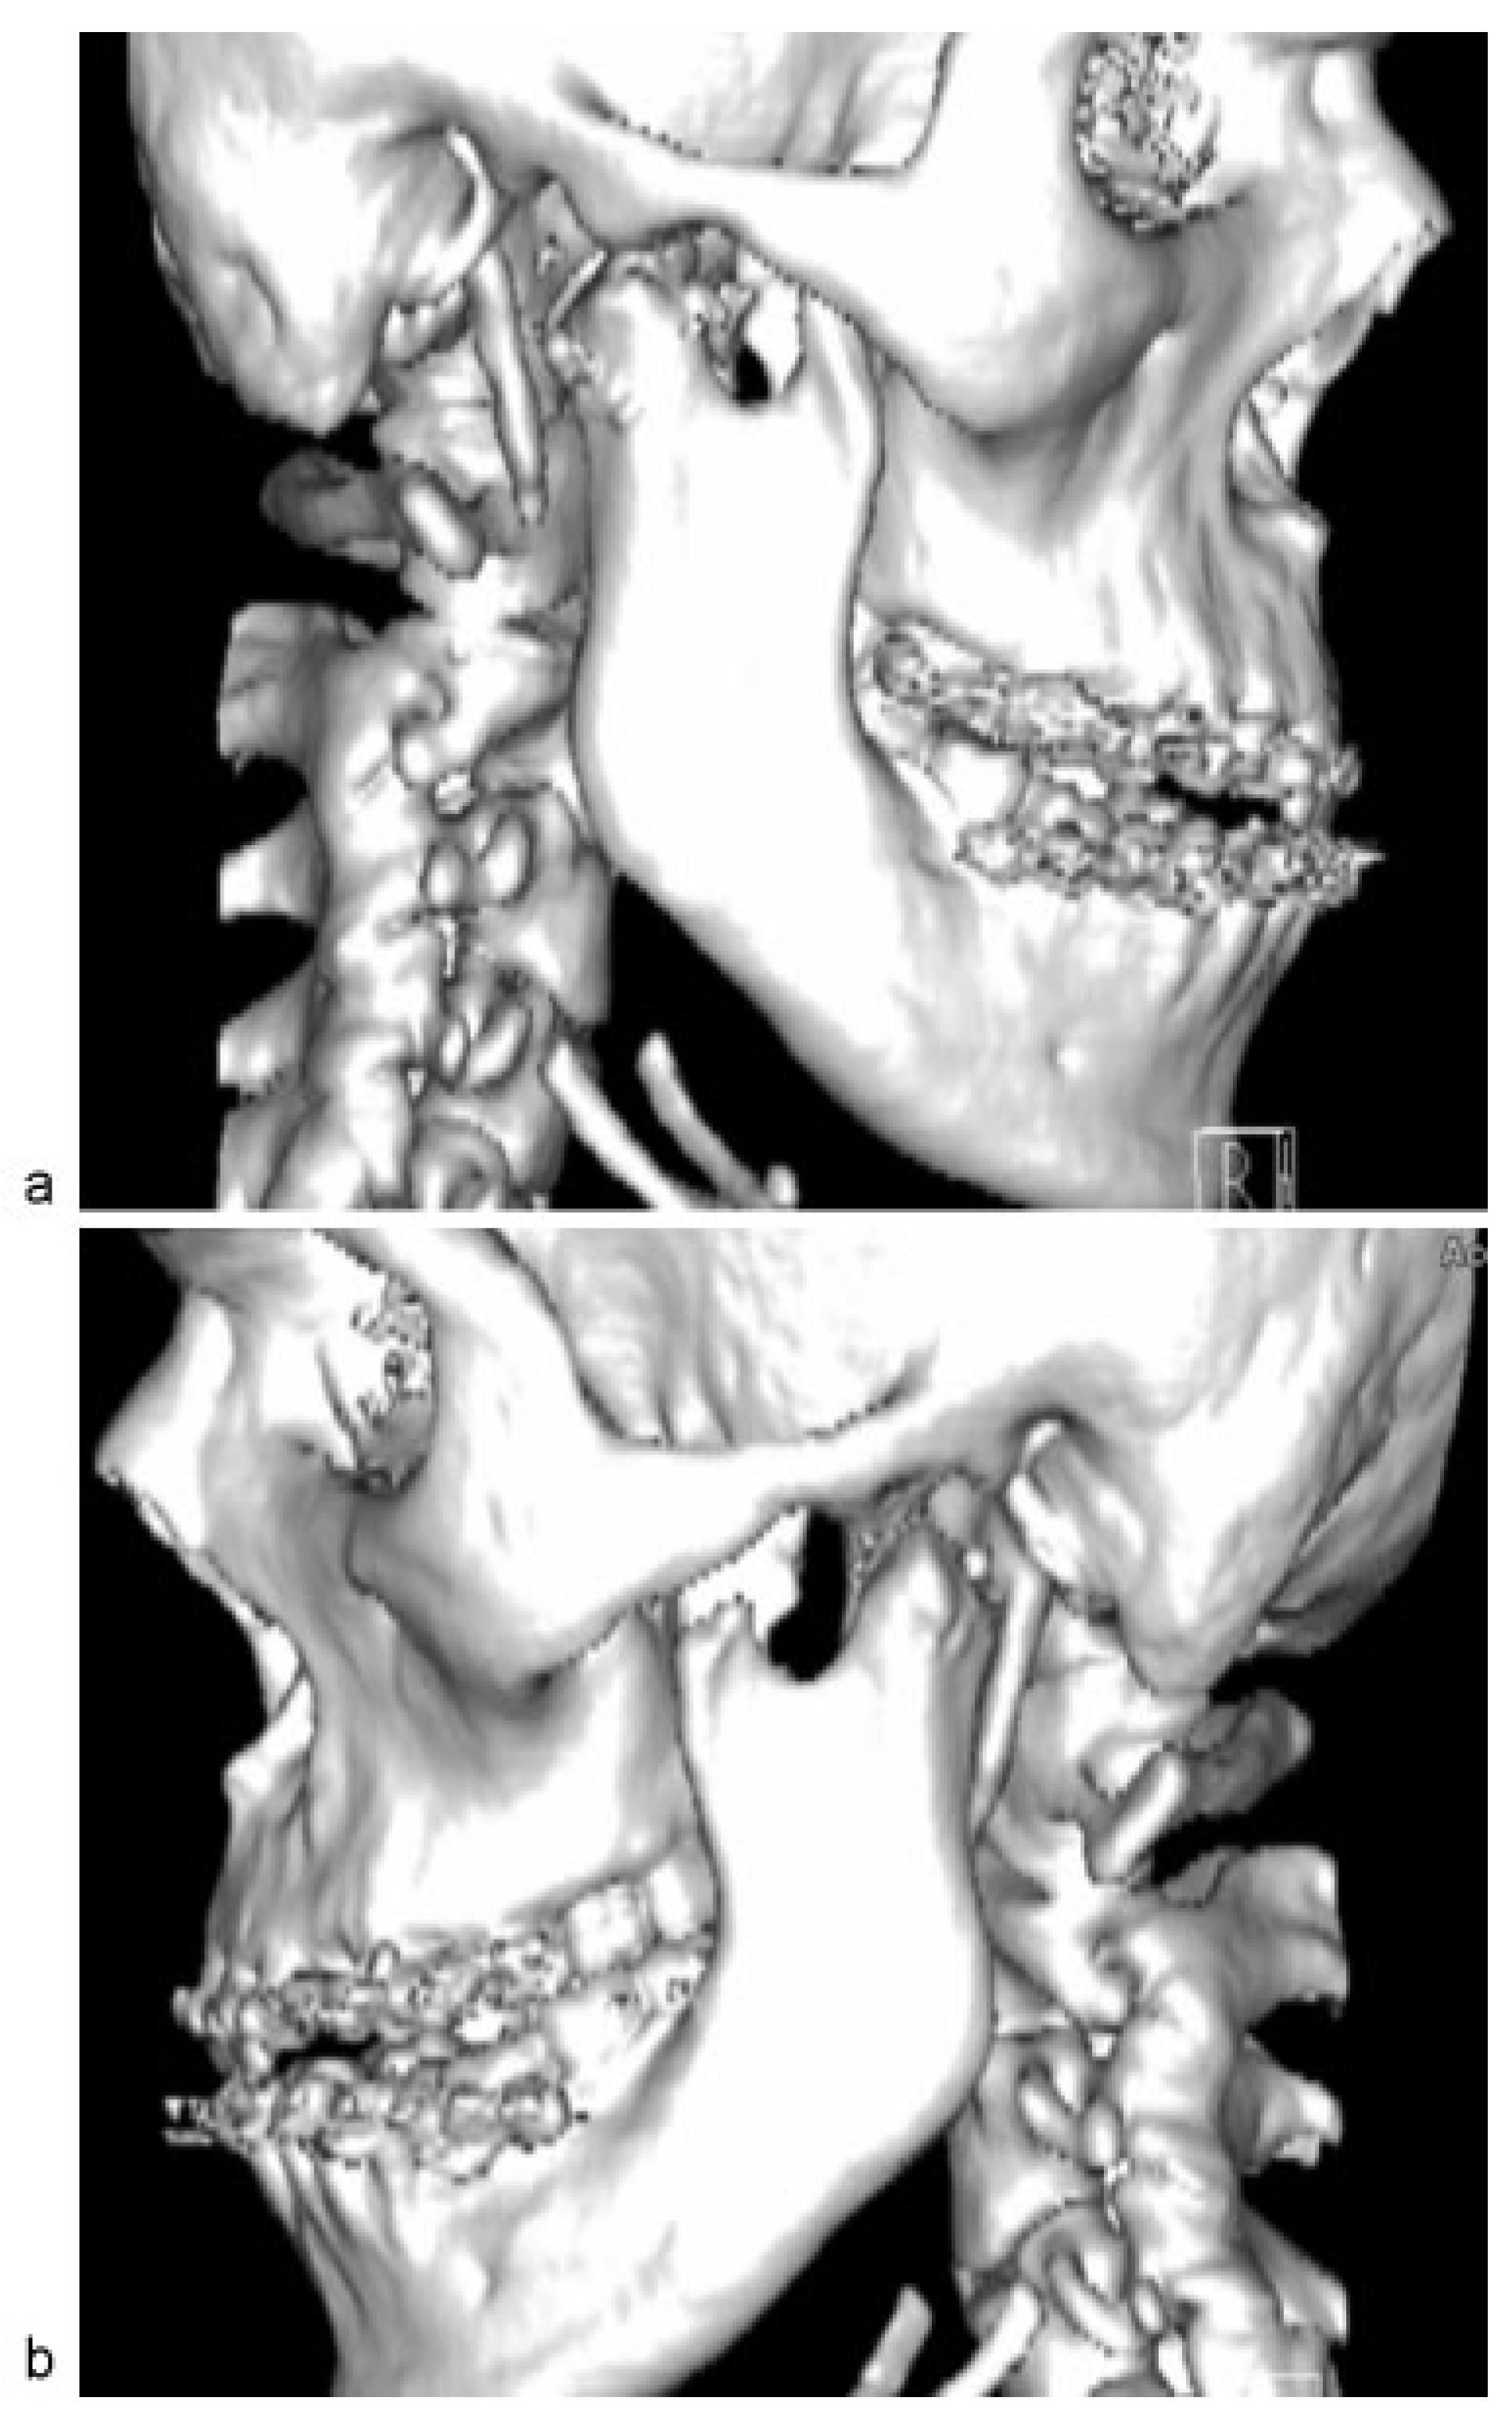

Arch bars were applied to upper and lower teeth. The patient was subjected to 2 weeks of intermaxillary fixation (IMF) to keep the condyles in new position and then continued on elastics training. CT scan immediately postoperative shows the right condyle inferior to the articular eminence and the left condyle inferior to the left glenoid fossa ([

Figure 5]). Postoperative 1 year review shows satisfactory occlusion ([

Figure 5.

(a) Right condylar head directly inferior to right articular eminence. (b) Left condylar head located inferior to left glenoid fossa.

Figure 5.

(a) Right condylar head directly inferior to right articular eminence. (b) Left condylar head located inferior to left glenoid fossa.